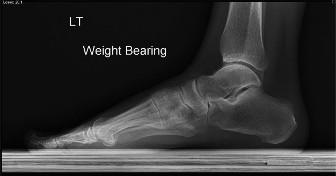

A 27-year-old, competitive triathlete sustained an injury to her left foot while trail running when she had a…